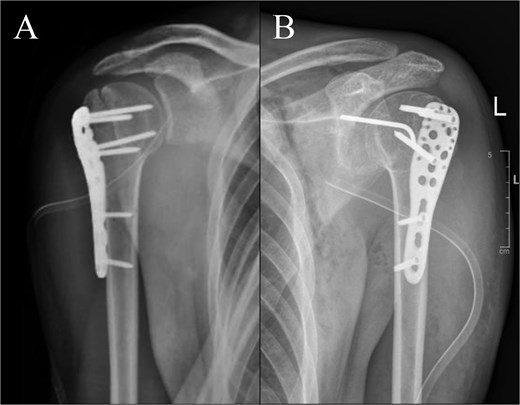

The patient was satisfied with the outcome, with normal activity regained 3 months after surgery. During the 1-year follow up of the right shoulder (Fig. 5), full ROM was achieved for flexion, extension, abduction, internal rotation, and external rotation (Table 1). Improvements of pain and functional score after 1 year was noticed with 0 visual analogue scale score, 100 The American Shoulder and Elbow Surgeons score and 0.8 disabilities of the arm, shoulder, and hand score. By the ninth month following the left shoulder surgery, improved ROM was noticed. Post-operative radiographic assessment of the right and left shoulders was conducted, as shown in Fig. 6.

Post-operative radiographs: (A) right shoulder; (B) left shoulder.